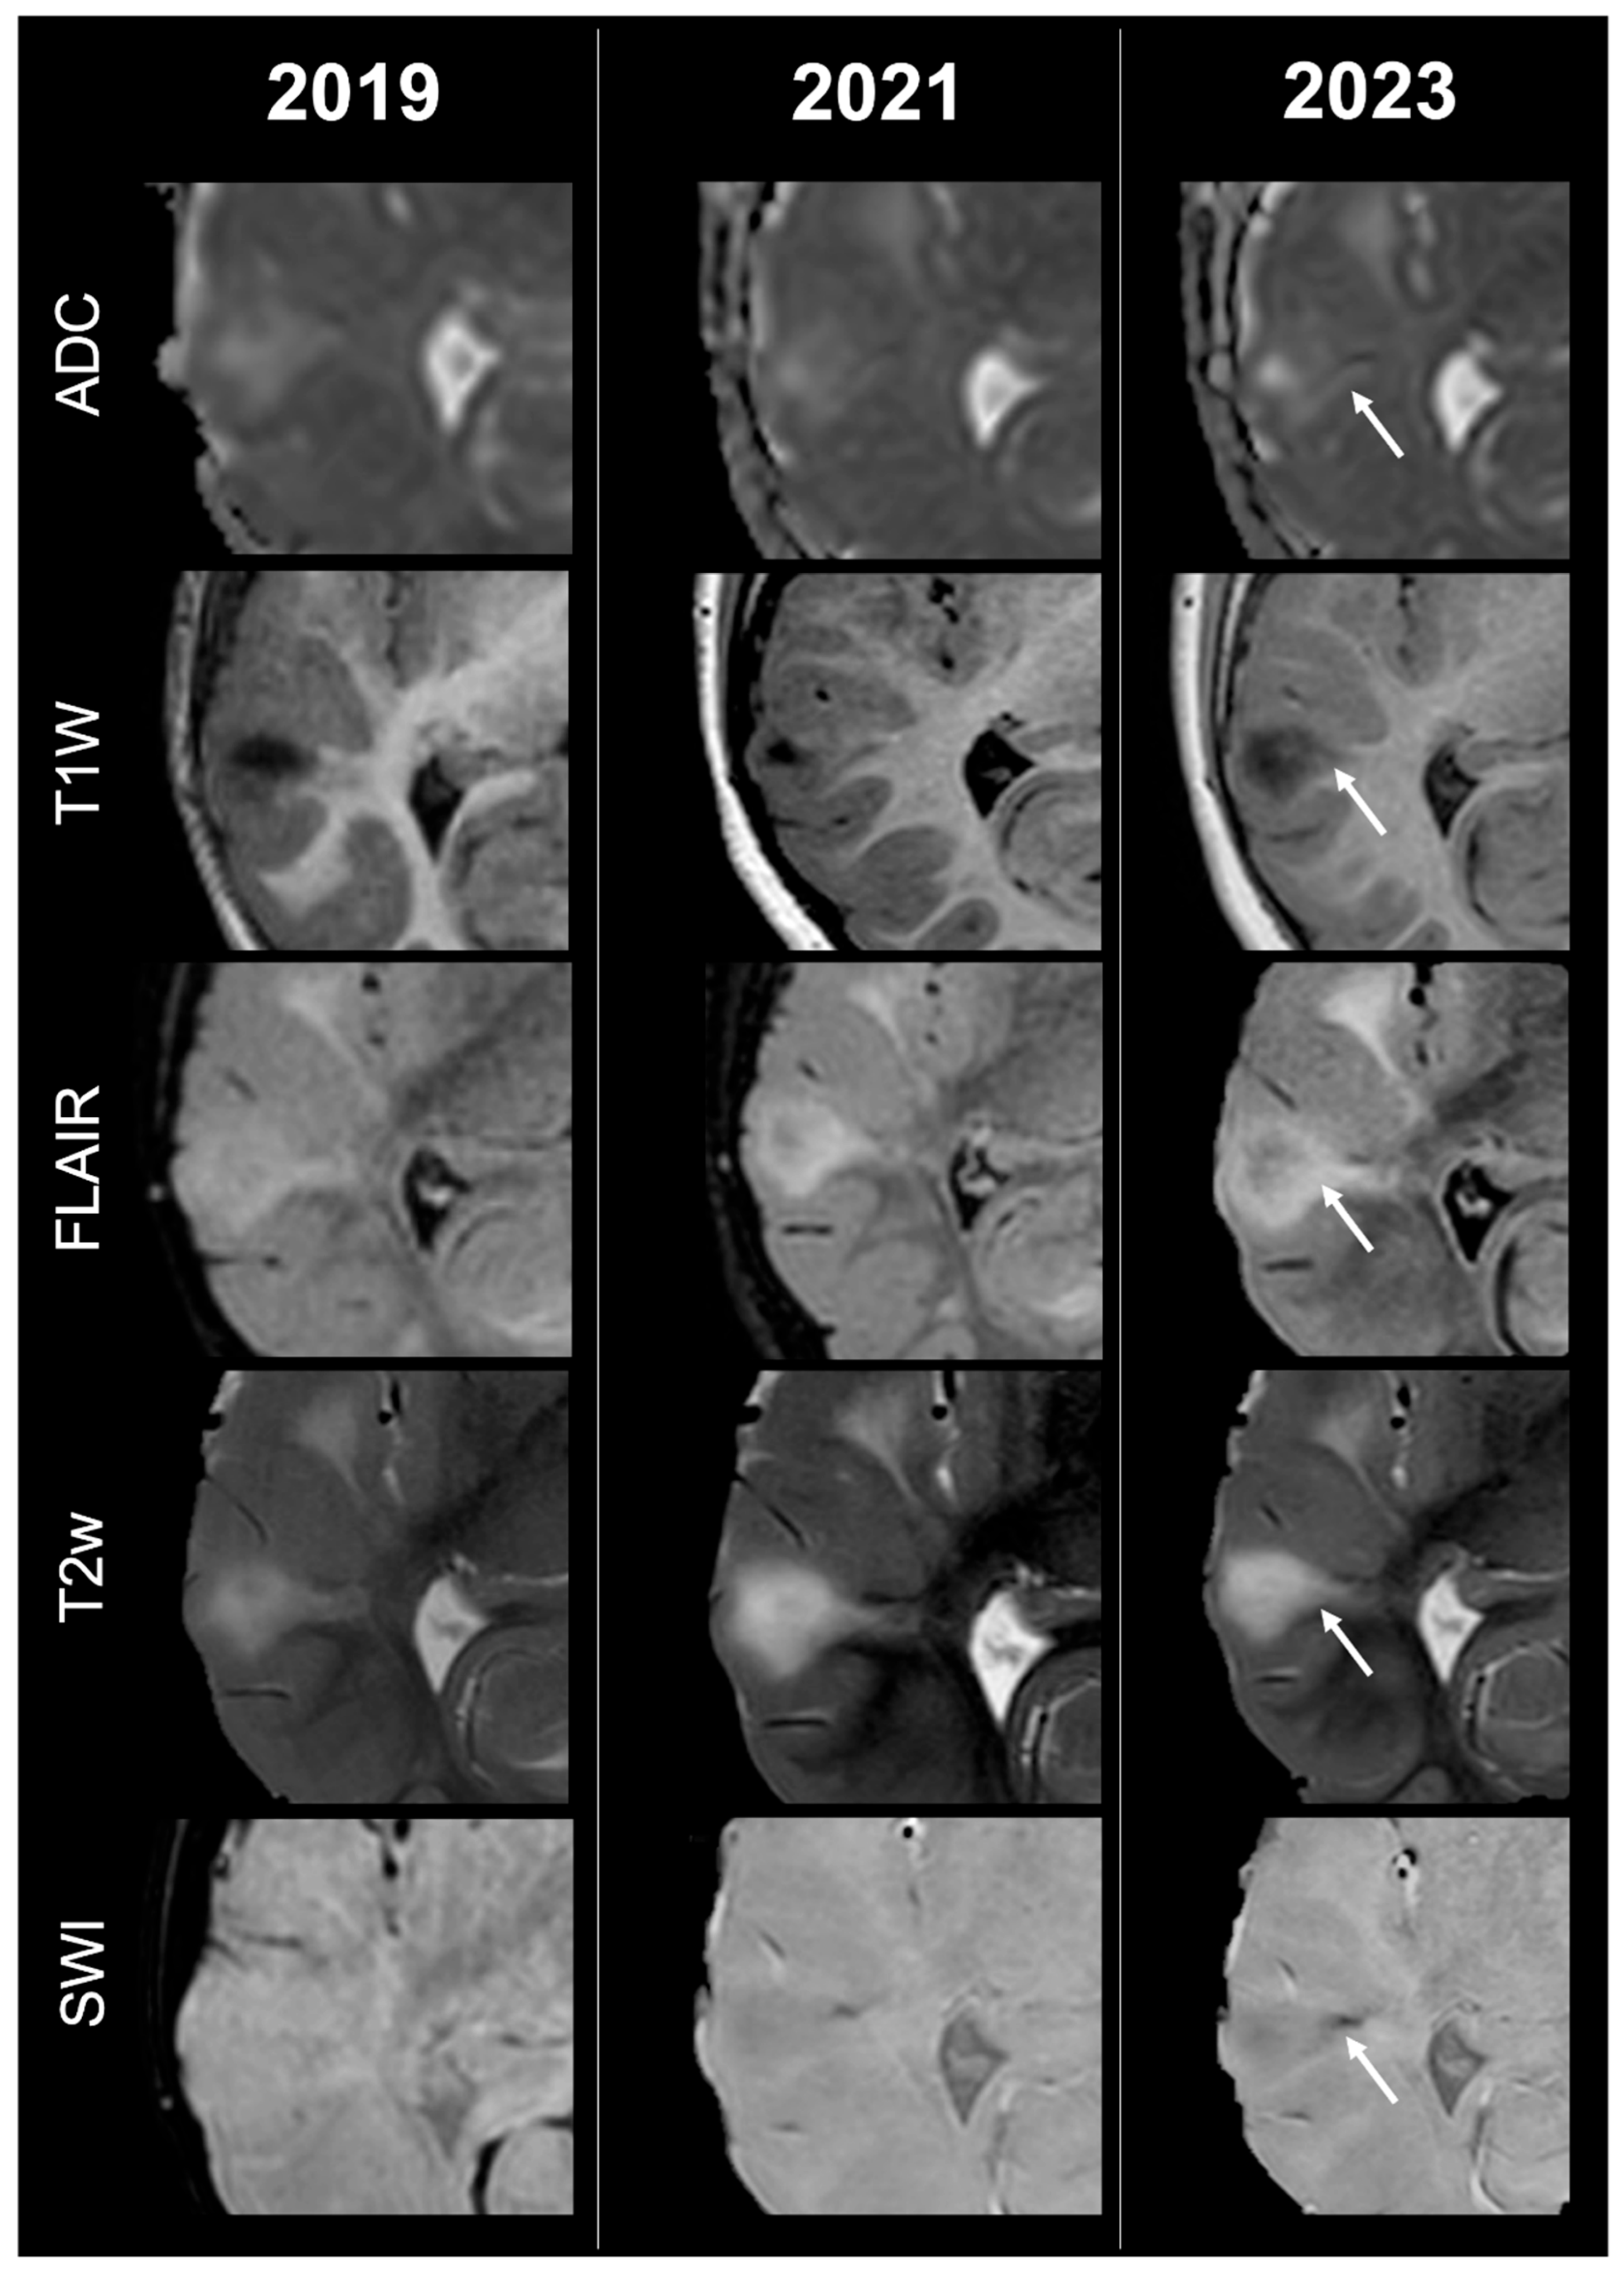

Concerning total lesion count, the interobserver agreement was excellent, with an ICC of 0.91 (95% CI: 0.87–0.95). At baseline, the total number of CTs identified across the cohort was 918 (mean ± SD = 16.1 ± 12.4), whereas at the last available MRI follow-up, the overall count increased to 1070 (mean ± SD = 18.8 ± 13.3), corresponding to a net gain of 152 CTs, equal to a relative variation of +17%. When stratified by tuber type, distinct trajectories were observed over time. Type A CTs, which were relatively abundant at diagnosis (N = 303, mean ± SD = 5.3 ± 7.0), decreased to 255 (mean ± SD = 4.5 ± 5.9) at follow-up, yielding a reduction of 48 lesions (−16%). Conversely, type B CTs showed an opposite trend, increasing from 438 (mean ± SD = 7.7 ± 8.4) at baseline to 556 (mean ± SD = 9.8 ± 8.6) at follow-up, corresponding to a net increase of 118 tubers (+27%). An example of MRI signal evolution from tuber A to tuber B is shown in Figure 1. Similarly, type C1 CTs rose from 160 (mean ± SD = 2.8 ± 4.8) to 220 (mean ± SD = 3.9 ± 5.8), with a net gain of 60 tubers (+38%). Type C2 CTs, initially rare at diagnosis (N = 14, mean ± SD = 0.2 ± 0.8), markedly expanded to 33 (mean ± SD = 0.6 ± 1.5), accounting for an increase of 19 CTs (+136%). Finally, type D CTs were only sporadically encountered, with a modest increase from 3 (mean ± SD = 0.1 ± 0.3) to 6 (mean ± SD = 0.1 ± 0.4), equating to a 100% variation. The observed increment of type C2 tubers was attributable almost exclusively to the progressive transformation of pre-existing type B lesions and, more prominently, type C1 lesions, while the increase in type C1 tubers reflected the gradual conversion of both type A and type B CTs that were already detectable at disease onset. An example of MRI signal evolution from tuber B to C1 is shown in Figure 2, while from tuber C1 to C2 in Figure 3. Only in one patient was a type C1 tuber newly identified at follow-up without clear evidence at baseline. In contrast, newly apparent tubers emerging over time but not clearly visible on baseline scans were most frequently represented by type A and type B lesions. Type D tubers were rare overall and were identified in only six lesions from four patients with a particularly high lesion burden; in all but one case they represented the evolution of type A or type B CTs (an example of MRI signal evolution from tuber A to tuber D is shown in Figure 4), while in a single case they were associated with adjacent subtle calcific foci. Overall descriptive data are summarized in Table 1.

Figure 1.

Left occipital tuber transition from type A to B at three different timepoints in a male patient diagnosed with TSC1.